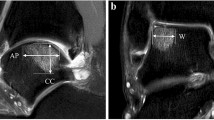

Preoperatively, all lesions were classified using MRI, as described by Hepple et al. [12]. Regarding the OLT size and the volume of the subchondral lesions, coronal width (W) was measured via the maximum extension within the coronal images. The anteroposterior length (AP) of the OLT and the depth of the subchondral lesions (D) were measured within the sagittal images. Then, the area of the OLT was calculated using the ellipse formula (W × AP × 0.79), and the volume of the subchondral lesions was determined using the standard volume of an ellipsoid (W × AP × D × 4/3π) [3, 29].

At the follow-up assessment, the post-operative OLT was assessed using CTA. The thickness of the repaired tissue was compared with the thickness of adjacent normal talar dome cartilage and classified into the following four grades: (0) no growth; (1) growth less than 50% of the adjacent normal cartilage thickness; (2) more than 50% of the adjacent normal cartilage thickness; and (3) similar to the thickness of adjacent normal talar dome cartilage (Table 1) [21, 32].

For the quantitative analysis of the degree of bone consolidation, the mean Hounsfield unit (HU) was obtained for the subchondral lesion of the OLT on one representative coronal or sagittal reconstruction CTA image [27]. The HU value was measured using manually drawn regions of interest (ROIs) on the CTA image [20].

Tissue growth and subchondral bony consolidation increased over time in most cases (Figs. 1, 2). Hypertrophic tissue and poor tissue growth were also observed. Uncontained shoulder lesions either restored the previous shape of the talus with cartilaginous signal or showed in situ tissue growth (Fig. 3). One lesion even achieved congruency of the joint by forming tissue growth at the confronting plafond surface (Fig. 3c). These lesions were classified as given in Table 3. A debrided OLT before microfracture is shown in Fig. 4.